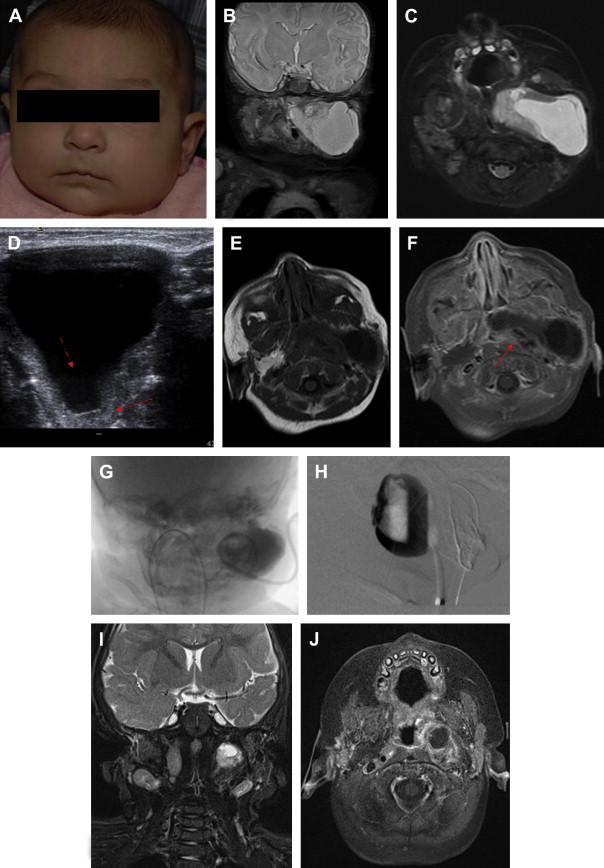

Example of an arteriovenous malformation. Pre(A, C) and... Download Interventional Radiology Vascular Malformation Our interventional radiologists clifford weiss and brian holly specialize in diagnosing and treating all forms of vascular malformations. Knowledge of the various malformations (including common conditions, such as venous malformation, arteriovenous fistula, and arteriovenous malformation) and vascular tumors allows for. Vms are the most common symptomatic vascular anomaly referred for intervention, usually due to thrombosis, swelling,. Interventional radiology may deliver. Interventional Radiology Vascular Malformation.